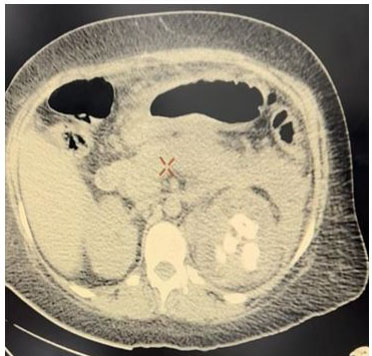

A simple abdomen CT scan was performed, finding an enlarged left kidney, with loss of morphology, striation of perirenal fat, thickening of Gerota’s fascia, dilation of minor calyces, presence of a hyperdense image on the large central portion compatible with staghorn stone and hypodense dots in upper left kidney pole compatible with gas in the collecting system (Figure 1 and Figure 2). Right kidney was with preserved dimension and morphology.

Figure 2: CT scan simple axial section. Enlarged left kidney, asymmetric, loss of cortex-medullary relationship, central hyperdense image compatible with staghorn stone, and dilation of minor calyces, perirenal fat changes, and thickening of the Gerota fascia.